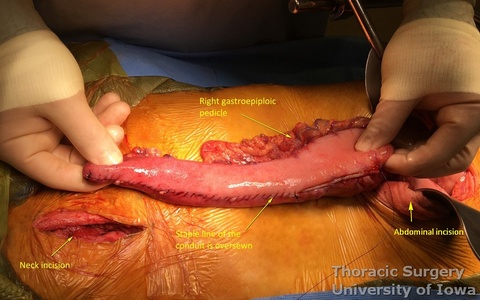

- Starting from the lesser curvature of the stomach, several stapler loads are sequentially fired towards the fundus of the stomach, thus creating a 4–5 cm wide gastric conduit and ensuring a 5 cm margin distal to the tumor. Depending on the thickness of the stomach, medium purple or thick black (alternatively blue or green, depending on manufacturer) loads are used.

- The gastric conduit stapler line is then oversewn with a running 4-0 (KP and JK) or 3-0 (EA) PDS.

- A Saratoga sump drain (or chest tube) is advanced from the cervical incision through the chest into the abdomen. A Penrose drain is sewn to the anterior wall of the gastric tube (in the area of expected gastrotomy for the anastomosis) and tied over the sump drain.

- The gastric conduit is gently delivered through the mediastinum into the neck without torsion.